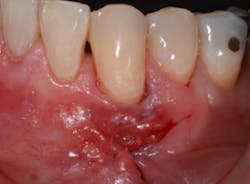

The Bernotti V-Y Flap involves making a submarginal supraperiosteal V-shaped incision 1 mm to 2 mm apical to the mucogingival junction, creating a pedicle flap (figures 2 and 2a). This flap is extended one tooth mesially and distally to the recession defect. It is important to note that the flap should leave the adjacent papillae intact in order to preserve blood supply. An intrasulcular incision is then made with a microsurgical blade to allow for coronal movement of the marginal tissue without tension (figure 3). The root is then scaled/root planed and chemically modified with an amoxicillin slurry for three minutes (figure 3a).

A horizontal mattress suture is then placed in the mucosa, which creates the vertical slope of the Y and advances the marginal part of the flap coronally above the recession defect (figures 4, 4a, and 4b). This tension-free coronal movement of the tissue is obtained by a zipper-like effect of the horizontal mattress (see the video at the end of this article).